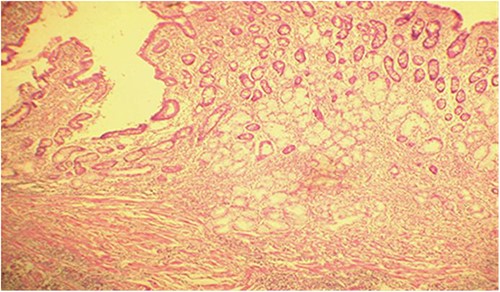

Microscopic analysis of various samples showed a transparietal massive infiltration of eosinophils with over 25% epithelial exocytosis and no granulomatous lesions or parasitic agents (Figs 3 and 4). Lymph nodes sampled from the congestive mesentery were reactive. The diagnosis of eosinophilic enteritis was established. The postoperative course was rapidly favorable, with weight gain. The patient was readmitted, and etiological assessment as well as a search for other locations, including hepatic and osteomedullary biopsies, returned negative results.

Diffuse infiltration of eosinophilic polymorphonuclear leukocytes affecting all layers of the jejunal wall (hematoxylin–eosin staining, magnification × 100).

Intraepithelial exocytosis of eosinophilic polymorphonuclear leukocytes (hematoxylin–eosin staining, magnification × 200).